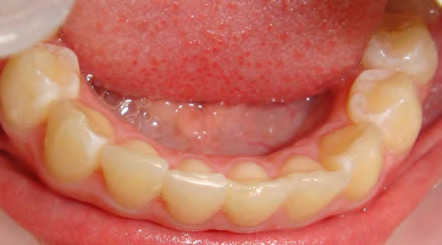

All of the patients below had been told they required extractions by orthodontists, some insisting that they could not be treated without extractions.

They were all treated without extractions, head gear or facemasks at Vakresmil and represent just a small sample of cases treated between 2004–2014.

The patient below had severe crowding of both upper canines and the lower right 5. The upper 4’s and 2’s were actually in contact.